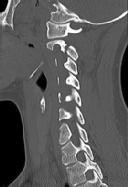

Figures 1 and 2 are CT scans obtained from a 68-year-old man who has had

progressive neck pain and stiffness, worsening gait imbalance, upper extremity weakness, early muscle fatigue, difficulty with fine motor control, and difficulty with activities of daily living over the past few years. On physical examination, he has a wide based stiff legged gait, generalized upper extremity weakness, dense sensory loss in the upper and lower extremities, and markedly brisk reflexes. What is the most appropriate treatment for this patient?

4. Posterior cervical laminoplasties from C3-6 Discussions: D

This patient has progressive myelopathy secondary to ossification of the posterior longitudinal ligament. Diagnostic imaging reveals multilevel cervical cord compression from C4-6. The patient has maintained reasonable cervical lordosis. A posterior procedure such as multilevel laminoplasty

decompresses the spine, is motion preserving, and has a low complication rate. Observation and cervical epidural injections are not viable options in patients with progressive myelopathy. Anterior cervical decompression, including corpectomy, is an option; however, anterior procedures have an increased risk of complications such as dural tear or cerebrospinal fluid leak. The axial CT image shows a "double layer" sign, which is consistent with dural ossification and increases the risk of dural injury with anterior decompression